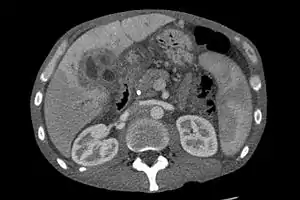

CT scan showing cholangiocarcinoma

Ultrasound of the liver and biliary tree is often used as the initial imaging modality in people with suspected obstructive jaundice.[48][49] Ultrasound can identify obstruction and ductal dilatation and, in some cases, may be sufficient to diagnose cholangiocarcinoma.[50] Computed tomography (CT) scanning may also play an important role in the diagnosis of cholangiocarcinoma.[51][52][53]